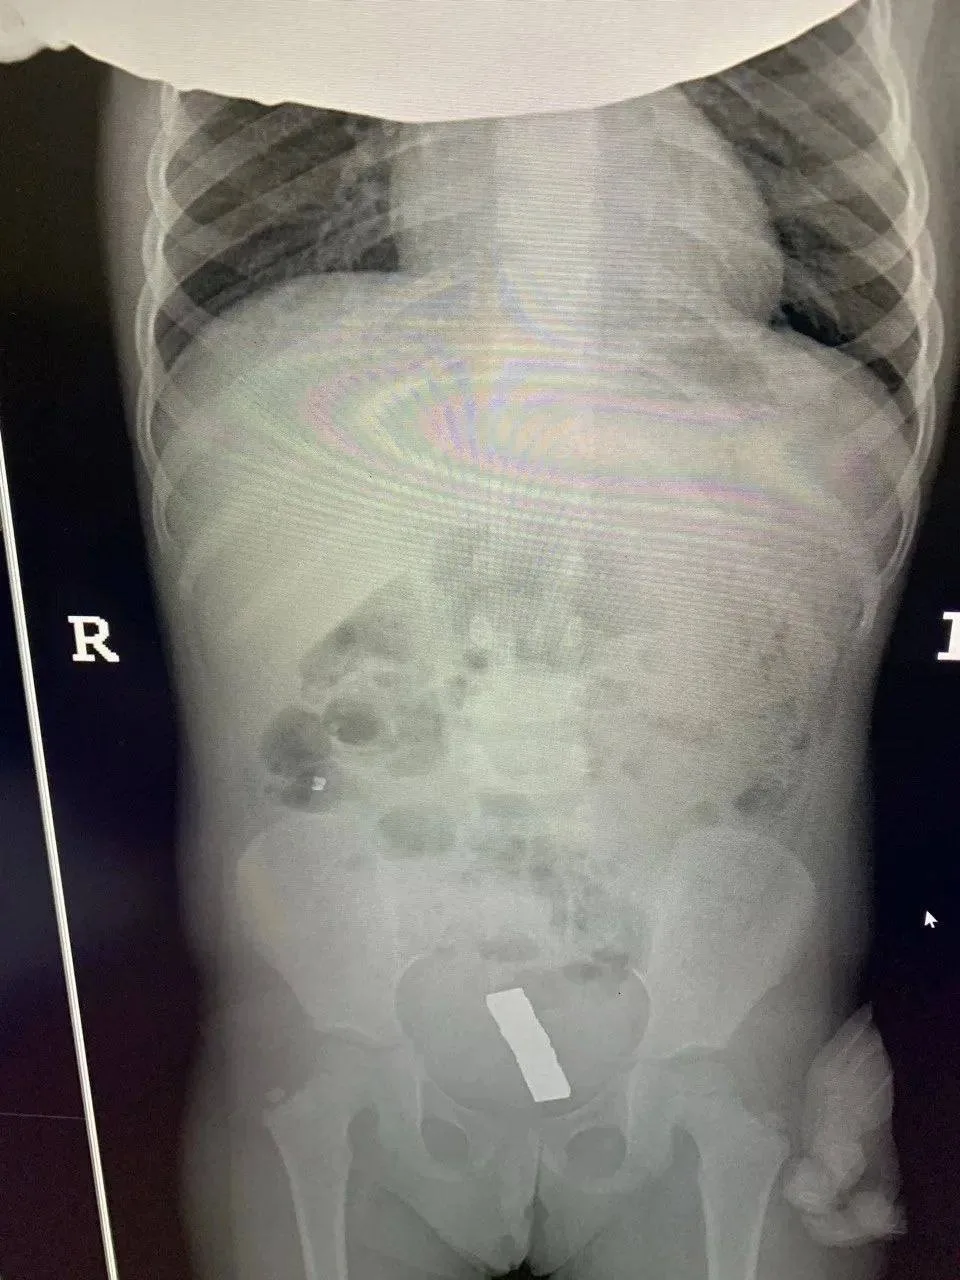

Девочка поступила в приёмное отделение филиала №2 с жалобами на сильные боли в животе. Пациентке провели рентген брюшной полости на котором было обнаружено наличие инородных тел металлического характера.

В отделении во время проведения лапароскопической операции было извлечено 15 неодимовых магнитов. В ходе операции было выявлено что инородные тела перфорировали кишку и находятся в малом тазу. Это усложнило ситуацию. Оставшиеся инородные тела были удалены.